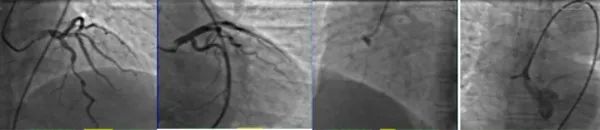

双绕行急诊冠脉造影

冠脉造影中左冠状动脉顺利到位,左前降支(LAD)中段中度狭窄,右冠状动脉未能顺利到位,可见右冠窦造影剂滞留。

主动脉CTA造影

患者回重症监护室(CCU)后立即行主动脉CTA造影,显示主动脉夹层(Standford A 型),破口位于升主动脉起始部,宽约7 mm;夹层范围为升主动脉至主动脉弓,累及头臂干起始部,右颈总动脉开口。双侧冠状动脉充盈不均匀,内可见低密度阴影。

根据造影结果,诊断考虑主动脉夹层累及双侧冠状动脉,右侧明显,1小时后病人不幸去世。